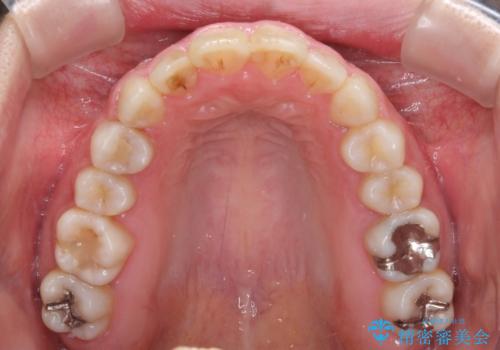

- ワイヤーではない矯正治療があると聞いたとのことで来院された患者様です。

長年前歯のデコボコを気にしていたもののワイヤー矯正に抵抗があり躊躇していたそうですが、インビザラインなら治療してみたいとのことで相談にいらっしゃいました。

インビザライン適用の歯列であったため、歯と歯の間を削るIPRを用いて改善することとしました。

お仕事柄、長時間のマウスピース装着が苦ではなかったので、歯列はすぐに整いましたが、ゆっくりとした交換頻度であったので、2年ほどの治療期間を要しました。